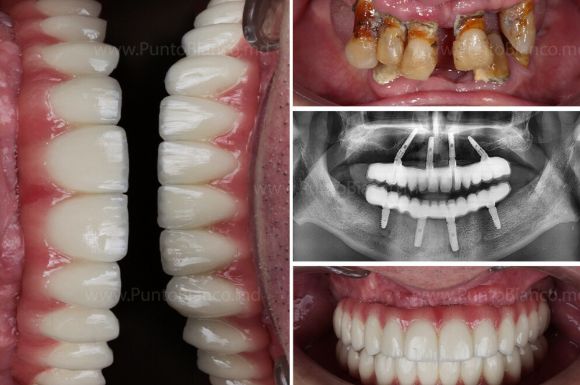

Implanturile dentare All-on-X reprezintă o revoluție în domeniul stomatologiei, oferind o soluție eficientă și permanentă pentru pacienții care se confruntă cu pierderea majorității sau a tuturor dinților pe o arcadă dentară. Această tehnologie avansată permite restaurarea întregii arcade dentare utilizând un număr minim de implanturi (de obicei 4 sau 6), strategic plasate pentru a asigura stabilitate și confort maxim.

Suntem printre puținele clinci stomatologice din Moldova care promit și chiar realizează atât inserarea implanturilor cât și dantura fixă provizorie în ziua intervenției sau a doua zi. Aceasta este posibil datorită tehnologiilor avansate de care dispunem în clinica Punto Bianco (amprente digitale realizate cu cel mai performant scaner intraoral, tomografii 3D direct in clinică, propiul laborator digital) dar și echipei multidisciplinare cu o experiență mare în reabilitări complete și complexe a danturii.